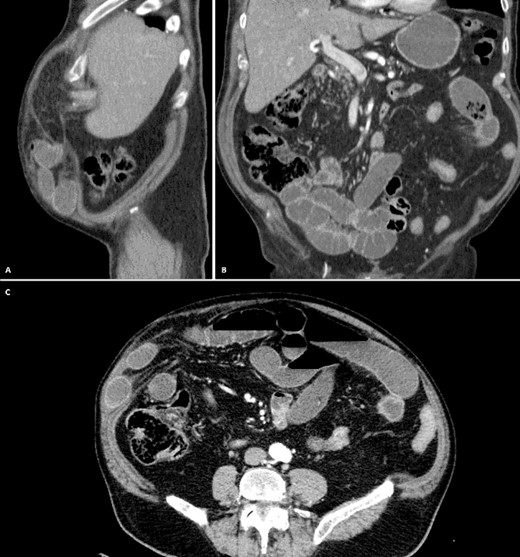

With these results, an abdominal CT revealed diffuse bowel obstruction; most of the small bowel was dilated (measuring > 4 cm in diameter), and there were loops of the bowel within the hernia that were enlarged with multiple air-fluid levels. We didn’t detect any mass on the liver or complications with the previous cholecystectomy. Bowel obstruction due to an incarcerated hernia was suspected Fig. 1A–C. With this, surgical consultation was needed, and surgery was decided.

A: CT, Multiple dilated bowel loops within the hernia. B: CT, No Pneumobilia is seen. C: CT, Diffuse dilation with multiple air-fluid levels.